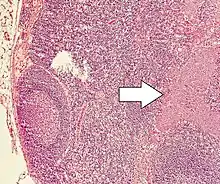

Lymph node metastasis of a neuroendocrine tumor

Currently there is no one staging system for all neuroendocrine neoplasms. Well-differentiated lesions generally have their own staging system based on anatomical location, whereas poorly differentiated and mixed lesions are staged as carcinomas of that location. For example, gastric NEC and mixed adenoneuroendocrine cancers are staged as primary carcinoma of the stomach.[40]